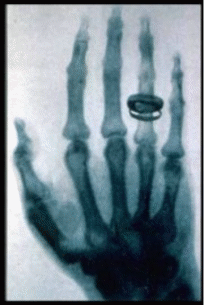

По этой причине Рентген не знал о сделанных до него открытиях и открыл лучи, названные впоследствие его именем, независимо - при наблюдении флюоресценции, возникающей при работе катодолучевой трубки. Рентген занимался Х-лучами немногим более года (с 8 ноября 1895 года по март 1897 года) и опубликовал о них всего три сравнительно небольших статьи, но в них было дано столь исчерпывающее описание новых лучей, что сотни работ его последователей, опубликованных затем на протяжении 12 лет, не могли ни прибавить, ни изменить ничего существенного. Рентген, потерявший интерес к Х-лучам, говорил своим коллегам: "Я уже всё написал, не тратьте зря время". Свой вклад в известность Рентгена внесла также знаменитая фотография руки его жены, которую он опубликовал в своей статье (см. изображение справа). Подобная слава принесла Рентгену в 1901 году первую Нобелевскую премию по физике, причём нобелевский комитет подчёркивал практическую важность его открытия. В 1896 году впервые было употреблено название "рентгеновские лучи". В некоторых странах осталось старое название - X-лучи. В России лучи стали называть "рентгеновскими" с подачи ученика В.К. Рентгена - Абрама Фёдоровича Иоффе.

(Рентгеновская фотография (рентгенограмма) руки своей жены, сделанная В.К. Рентгеном)